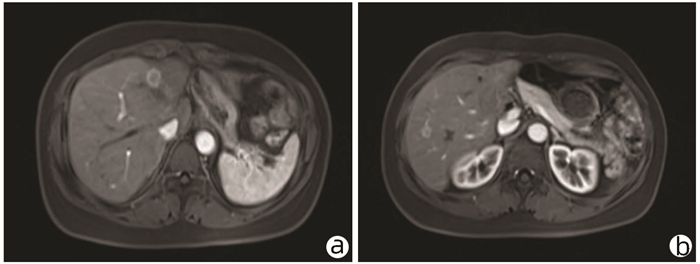

Clinical and pathological features of progressive familial intrahepatic cholestasis type 3

Yuhang WENG, Qingfang XIONG, Duxian LIU, Xulei ZHANG, Yongfeng YANG

2022, 38(1): 154-159. DOI: 10.3969/j.issn.1001-5256.2022.01.024

Abstract(1841) HTML (764) PDF (2621KB)(137)

Abstract:

Objective  To investigate the clinical and pathological features of progressive familial intrahepatic cholestasis type 3 (PFIC3).  Methods  A retrospective analysis was performed for 1326 patients with unexplained liver disease who attended Nanjing Second Hospital from January 2017 to December 2019, among whom 8 patients were diagnosed with PFIC3 based on clinical/pathological manifestation and gene sequencing results (1 patient did not undergo liver biopsy due to contraindication). Clinical, laboratory, imaging, and pathological findings were analyzed and a literature review was performed for the pathology of ABCB4-related diseases to summarize the clinical and pathological features of PFIC-3.  Results  Among the 8 patients with PFIC3, there were 5 male patients and 3 female patients, with a median age of 29.5 years. Of all 8 patients, 4 (50%) manifested as chronic cholestasis and 4 (50%) manifested as biliary cirrhosis, among whom 3 (75%) had the manifestation of portal hypertension. As for biochemical examination, 75% (6/8) had an increase in alkaline phosphatase, and 100% (8/8) had an increase in gamma-glutamyl transpeptidase. As for imaging examination, 50% (4/8) had cholecystitis, 25% (2/8) had gallstones, 25% (2/8) had bile duct dilatation, 75% (6/8) had splenomegaly, and 25% (2/8) had liver cirrhosis. As for liver biopsy, all 7 patients manifested as bile duct injury and/or reduction, and 57.1% (5/7) had absence of the bile duct. Multidrug resistance P-glycoprotein 3 (MDR3) immunohistochemical staining showed normal expression in 42.9% (3/7) of the patients and reduced expression in 57.1% (4/7) of the patients. Literature review obtained 17 articles with a description of the bile duct or MDR3 immunohistochemistry. Among the 7 patients with low phospholipid-associated cholelithiasis, 71.4% (5/7) had normal bile duct, 14.3% (1/7) had bile duct reduction, and 14.3% (1/7) had absence of the bile duct; among the 6 patients with intrahepatic cholestasis of pregnancy, 16.7% (1/6) had normal bile duct, 50% (3/6) had bile duct reduction, and 33.3% (2/6) had absence of the bile duct; among the 8 patients with PFIC3, 25% (2/8) had bile duct reduction and 75% (6/8) had absence of bile duct; among the 21 patients with PFIC3, 9.5% (2/21) had normal expression of MDR3, 23.8% (5/21) had a reduction in the expression of MDR3, and 66.7% (14/21) had absence of the expression of MDR3.  Conclusion  PFIC3 mainly manifests as cholestasis, cholelithiasis, and hepatic fibrosis. Pathological manifestation includes bile duct injury and bile duct reduction or absence of the bile duct in severe cases, and the degree of injury is associated with disease severity. MDR3 immunohistochemistry may show normal expression, reduced expression, or absence of expression, and diagnosis cannot be excluded in patients with normal expression. Genetic testing can be performed for diagnosis when necessary.